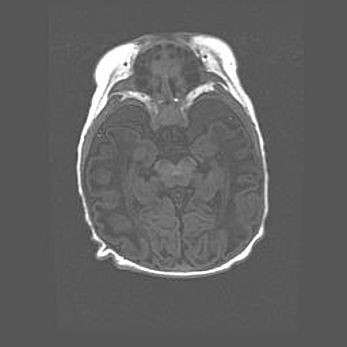

Сообщающаяся гидроцефалия. Кистозная энцефаломаляция головного мозга.

Возраст: 3 месяца 4 дня

Вес: 3100 г

Пол: женский

Окружность головы: 34 см

Срок гестации: 31 неделя

Кистозная энцефаломаляция головного мозга - одна из форм поражения головного мозга в детском возрасте. Характеризуется возникновением множественных и распространённых кист в коре, белом веществе и подкорковых образованиях головного мозга у плодов, новорождённых и детей раннего возраста. Развитие кистозной энцефаломаляции связано с внутриутробной асфиксией и гипотонией, родовой травмой, тромбозом синусов, пороками развития сосудов, инфекциями, сепсисом и другими причинами. Наиболее значимые инфекционные агенты: вирусы простого герпеса, цитомегалии, краснухи, токсоплазмы, энтеробактерии, золотистый стафилококк и другие.